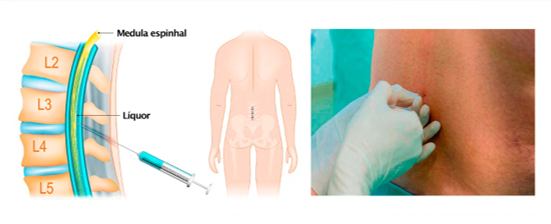

– Punção lombar

FONTE: próprio autor.